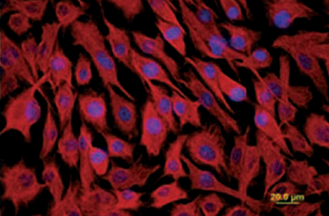

- Effects of antifungal drugs and delivery vehicles on morphology and proliferation of equine corneal keratocytes in vitro